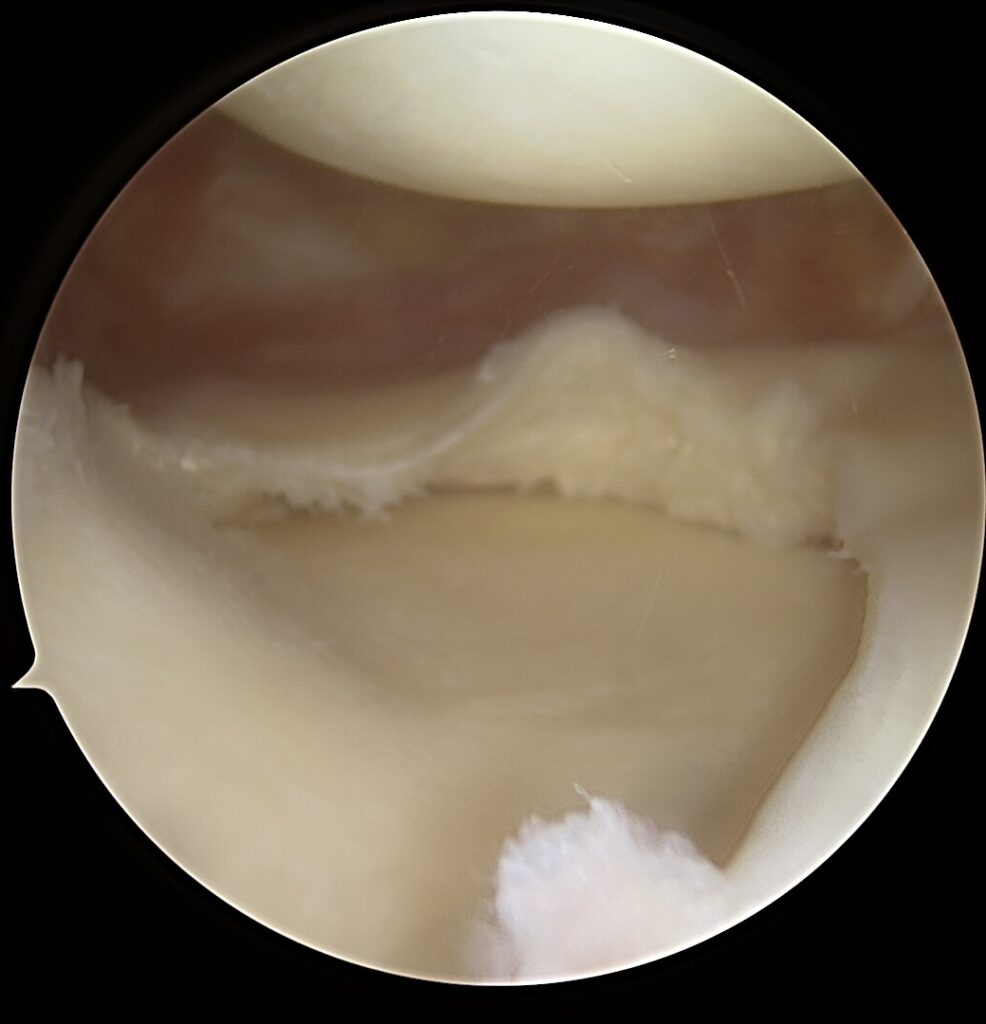

Vidinis kelio stabilumas priklauso ne tik nuo MCL, bet ir nuo įstrižinio (POL) raiščio, kuris kontroliuoja:

- užpakalinį – vidinį kelio sąnario nestabilumą